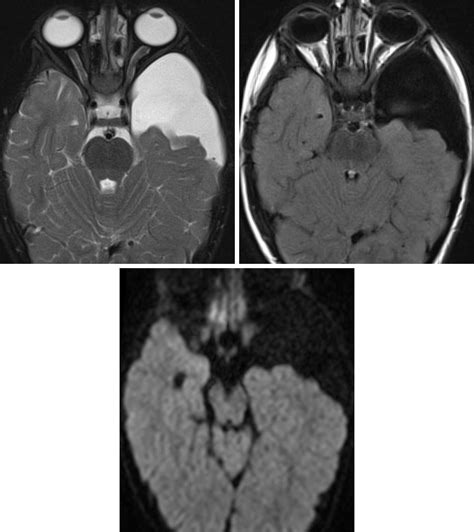

Diagnosing a cyst in brain typically involves a combination of medical history, physical examination, and imaging tests. The most common diagnostic tools include:

• Magnetic Resonance Imaging (MRI)

• Computed Tomography (CT) scan

MRI is often the preferred method for diagnosing brain cysts because it provides detailed images of the brain and can help differentiate between different types of cysts. CT scans are also useful and can be particularly helpful in emergency situations where quick imaging is needed.